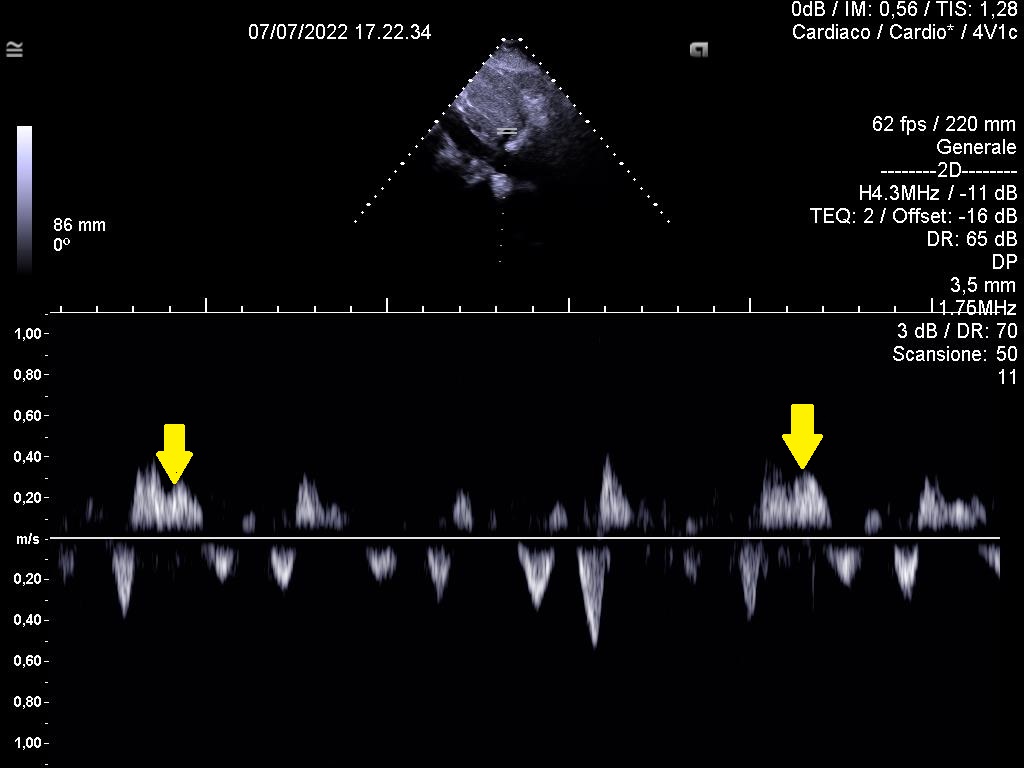

2⃣ E/A variation at the level of MV inflow.

Respiratory variation of peak E wave velocity should be at least >15%.

Inspiratory decrease and expiratory increase of E wave vel. (not so prominent here)